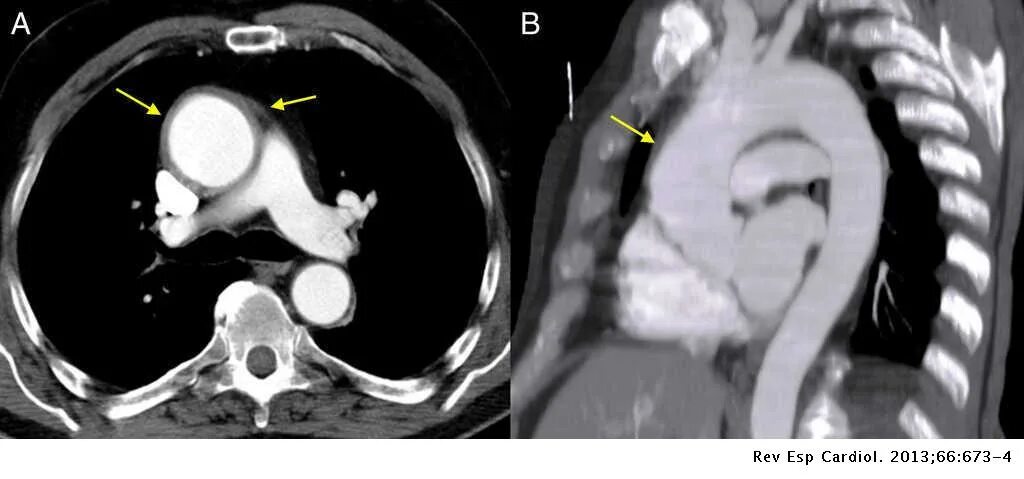

Аневризма аорты мкб 10